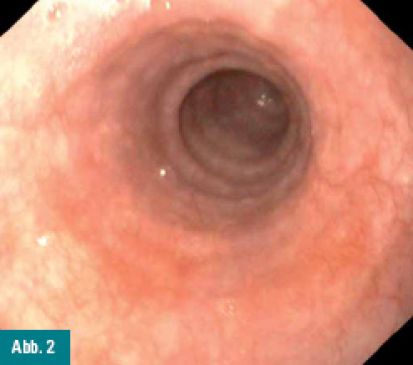

Abbildung 1 und 2: Weißlichtendoskopie des proximalen Ösophagus, das linke Bild zeigt die makroskopischen Auffälligkeiten.